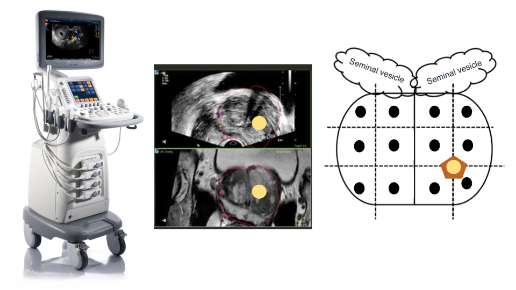

Технологическое развитие медицинского оборудования привело к возможности совмещения снимков МРТ и УЗИ; такая технология получила название «фьюжн». Это позволяет, при наложении друг на друга и синхронизации МРТ-изображения и ультразвукового изображения, произвести точечный забор материала из подозрительного фокуса, диагностированного на МРТ. Информативность такого исследования значительно превосходит информативность стандартной методики и снижает вероятность получения ложноотрицательных результатов.